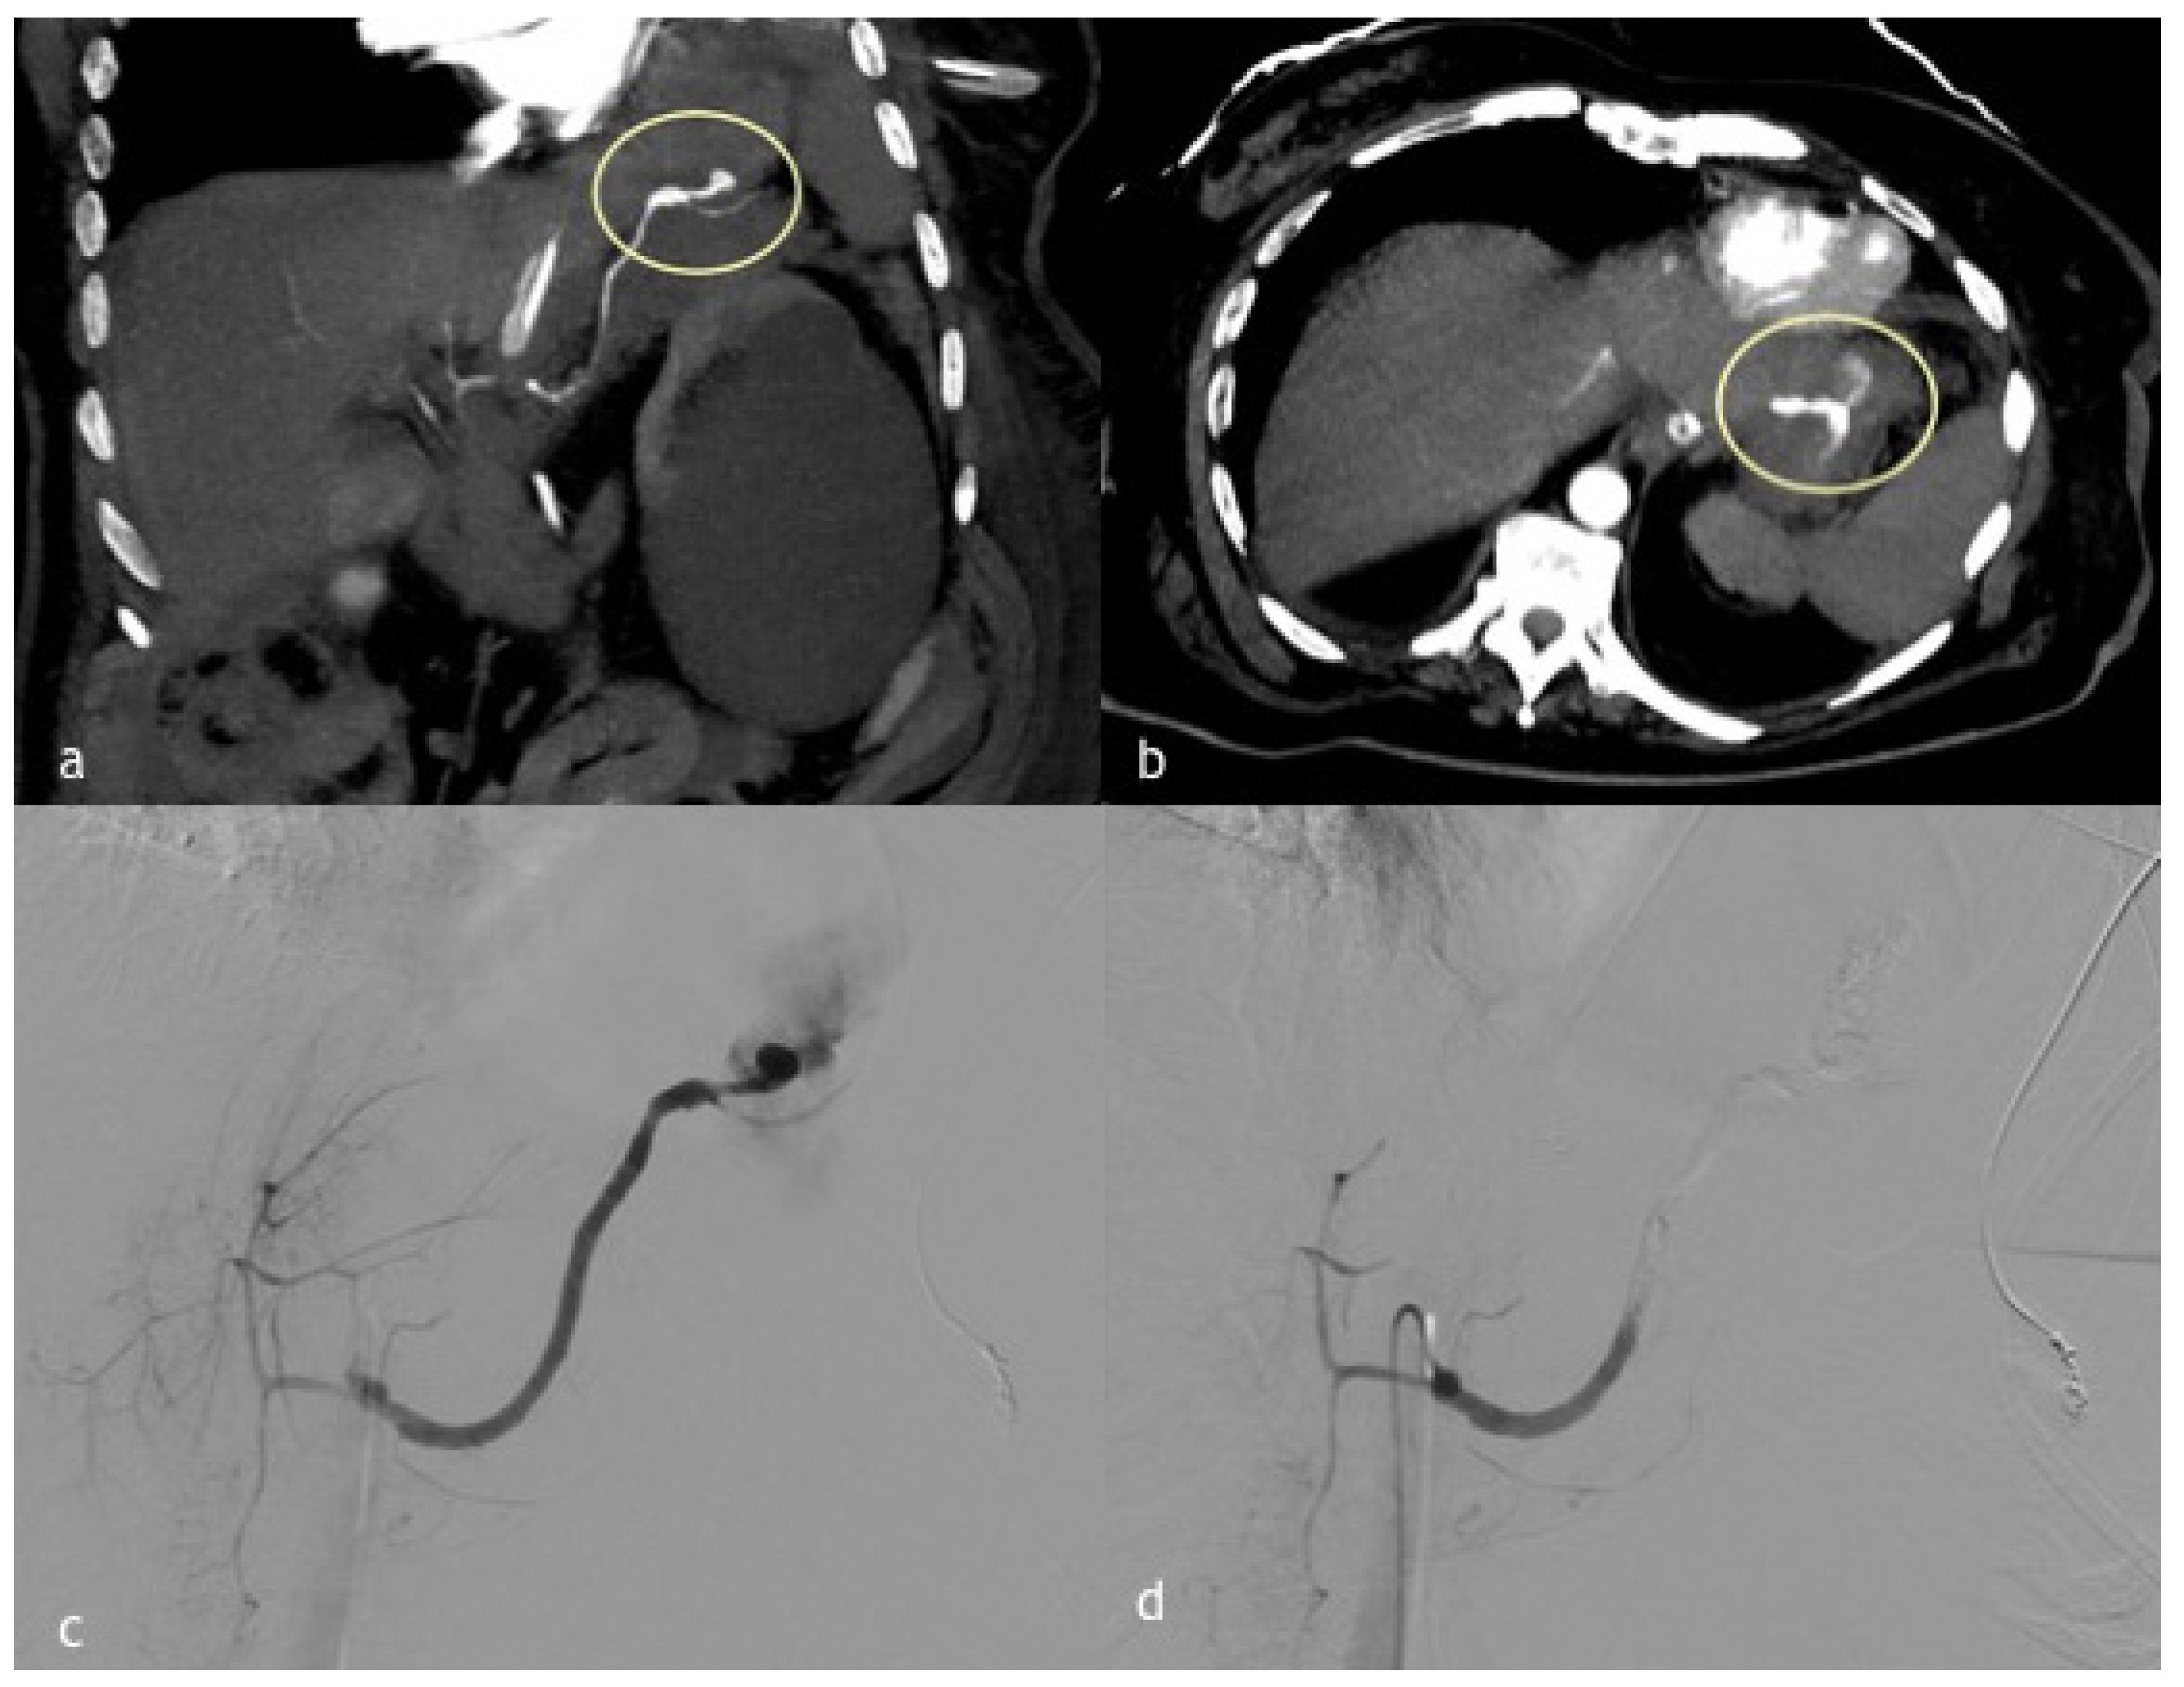

Figure 1. (ad). A 60-year-old man with a walled off necrosis after necrotizing pancreatitis. (a,b) Axial and sagittal MPR reconstruction images demonstrate splenic artery PSA (circle) in direct connection with a walled-off necrosis, previously treated surgically. (c) Angiographic images of splenic artery PSA (arrow in (c)). (d) Final angiographic control after coil embolization demonstrates splenic artery recanalization distal to coil embolization by magna pancreatic artery.